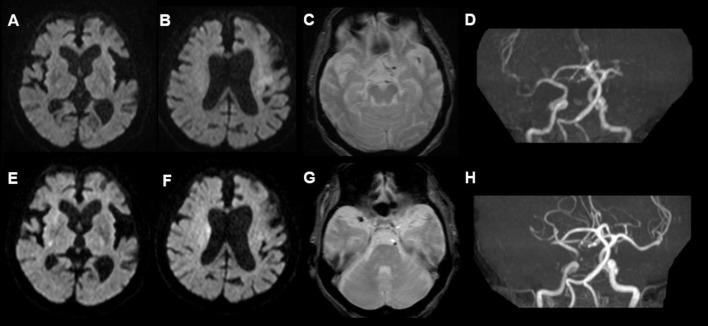

An 83-year-old Japanese woman developed right hemiplegia and motor aphasia three days after receiving her first dose of the BNT162b2 (Pfizer) COVID-19 mRNA vaccine. She had been taking rivaroxaban for persistent atrial fibrillation for 10 years, but had no symptomatic ischemic strokes. On magnetic resonance imaging (MRI) the left middle cerebral artery (MCA) was occluded. Intravenous recombinant tissue-plasminogen activator (rt-PA) therapy and mechanical thrombectomy were performed, and she recovered almost fully. However, three days after the second dose, she developed left hemiplegia and left hemispatial neglect. MRI showed occlusion of the right MCA. Only mechanical thrombectomy was performed again, but it could not be resumed due to the hard thrombus.

一名 83 岁日本女性在接种 BNT162b2(辉瑞)COVID-19 mRNA 疫苗第一剂后 3 天出现右侧偏瘫和运动性失语。她因持续性心房颤动已服用利伐沙班 10 年,但无症状性缺血性脑卒中。磁共振成像(MRI)显示左侧大脑中动脉(MCA)闭塞。给予静脉内重组组织型纤溶酶原激活剂(rt-PA)治疗和机械血栓切除术,她几乎完全恢复。然而,在第二剂后 3 天,她出现左侧偏瘫和左侧半空间忽略。MRI 显示右侧 MCA 闭塞。再次仅行机械血栓切除术,但由于血栓过硬,无法恢复。